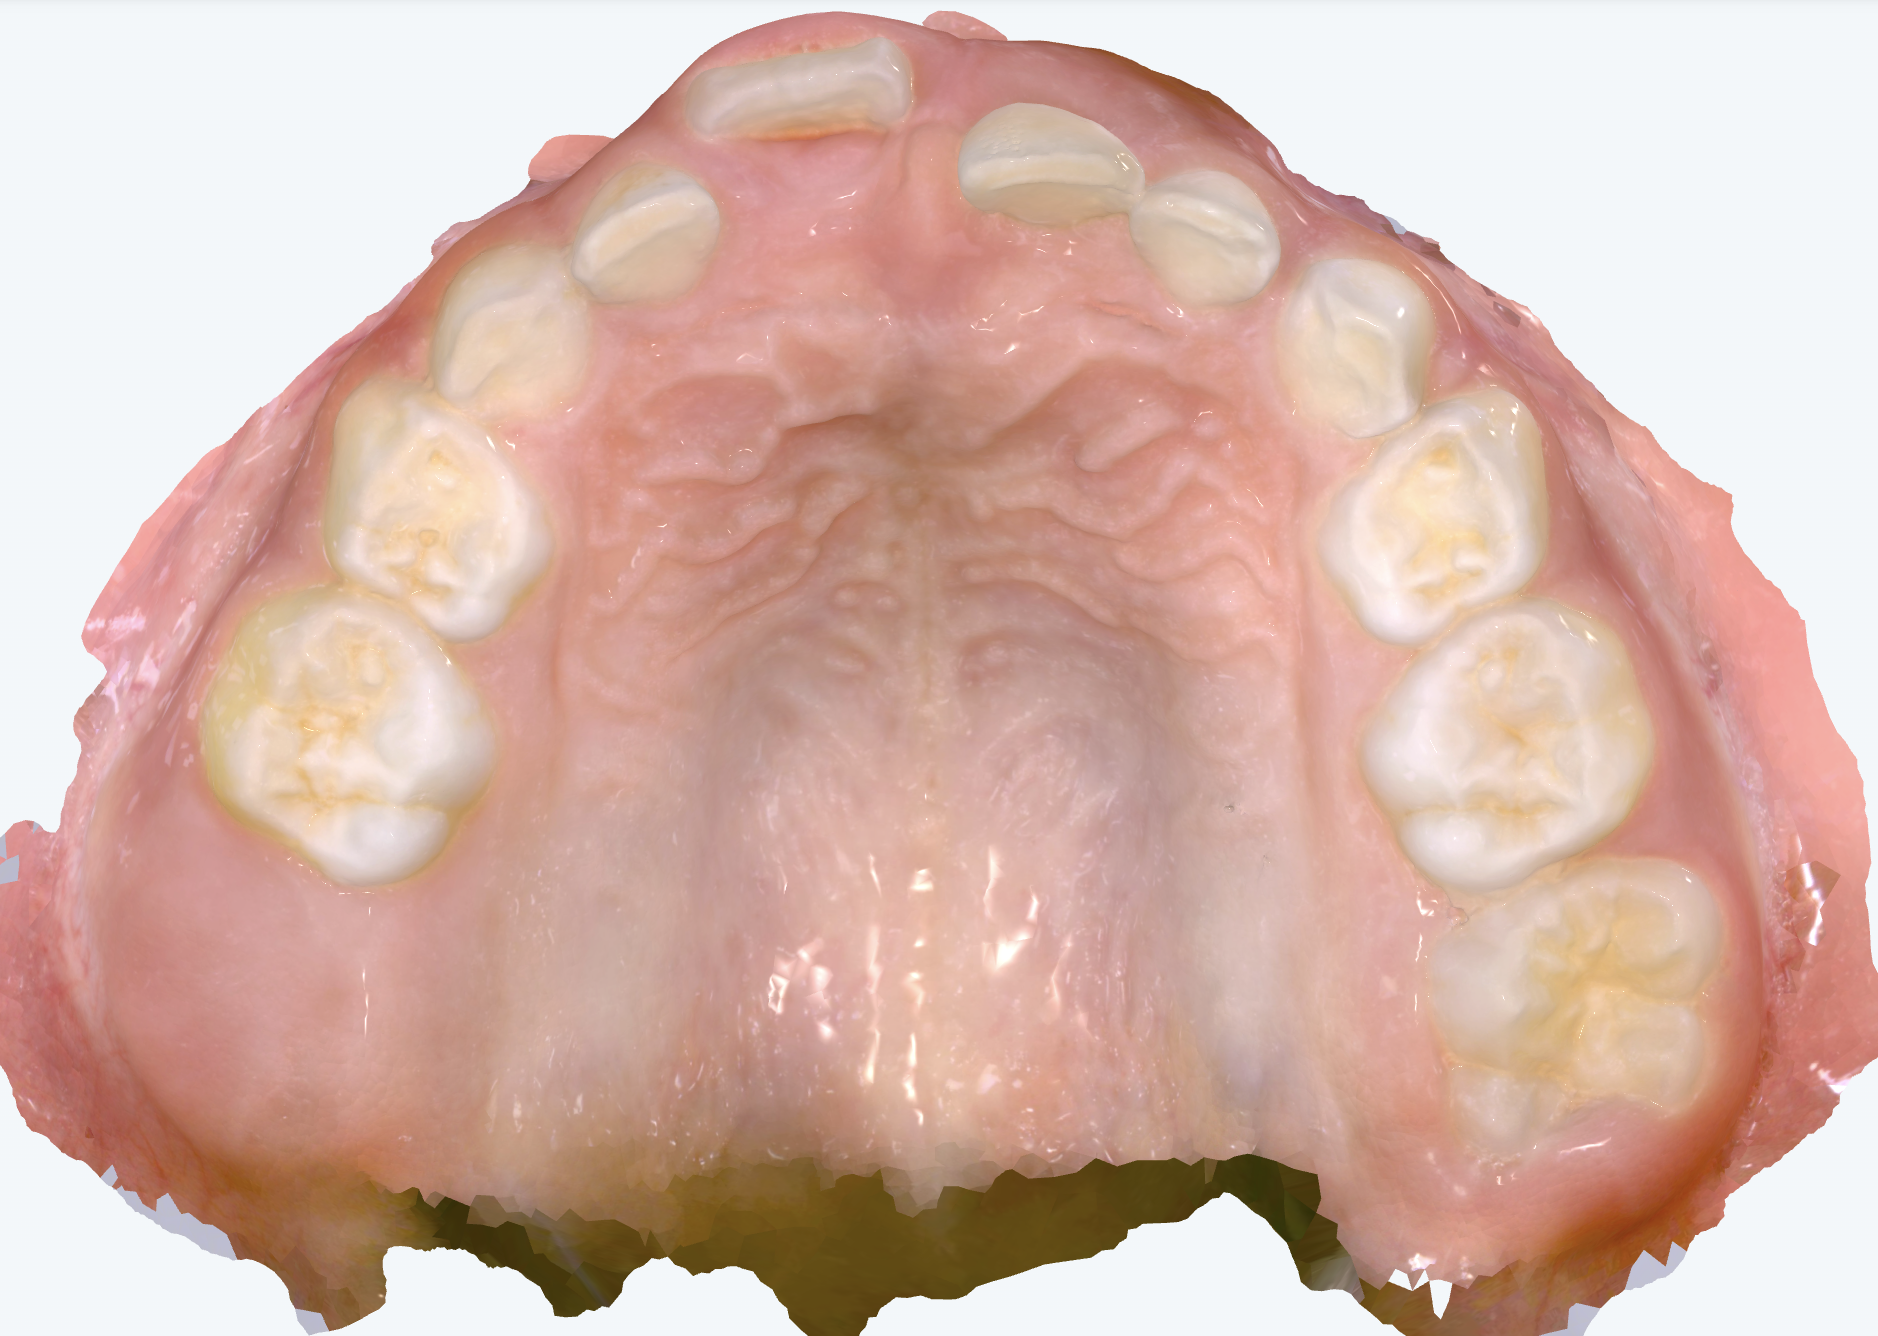

初診時の画像診断

上下の前歯の歯並びにガタガタがあります。

右上の前から1番目の歯が大きく前に出ています。